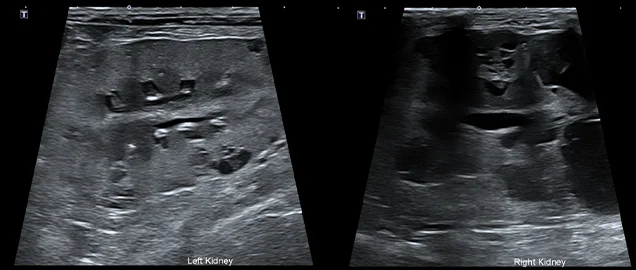

초음파 검사에서는 신장의 피질과 수질이 구분되지 않고, 실질 내 다수의 낭종이 있는 형태학적 변화가 확인되어 유전적 신장 기형 및 만성적인 신장 기능 저하가 있었던 것으로 의심되었습니다.

현재 신장 수치가 양호하게 개선되고 있으며, 정기적인 신장 수치 모니터링 및 초음파 검사를 통해 꾸준히 관리할 예정입니다.